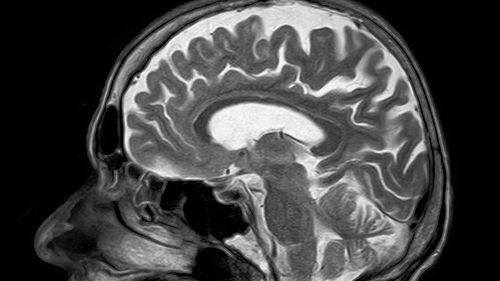

뇌에 축적된 노화 세포(일명 좀비 세포)를 제거하면 비만으로 인한 불안증을 완화할 수 있다는 연구결과가 나왔다고 유전·생명공학 전문매체 '젠(GEN; Genetic Engineering & Biotechnology News)'이 7일(현지시간) 보도했다.

연구팀은 특히 비만 상태인 사람의 뇌에 쌓인 노화 세포가 불안증을 높이면서 신경정신학적 기능에 이상을 일으킨다는 점에 착안했다.

연구팀은 불안증을 통제하는 생쥐의 측두 뇌실(lateral ventricle)에 지질이 쌓이자 노화 세포도 급격히 늘어난다는 사실을 확인했다.